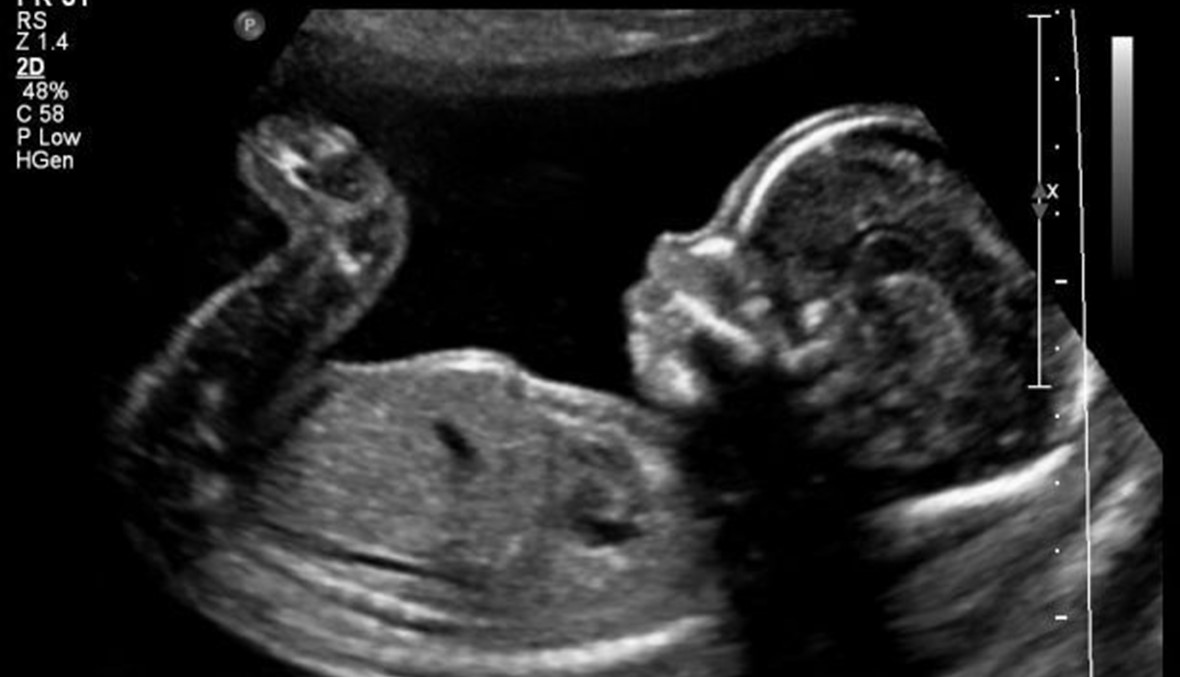

أثارت صورة طفل ولد بتشوه خلقي في مستشفى السلام في طرابلس، ضجَّة إعلامية بين الرأي العام والطاقم الطبي. فالطفل الذي يعاني من خلل توفي بعد 24 ساعة من ولادته. ما طرح أسئلة عدَّة حول كيفية ولادة جنين مشوَّه؟ وما هي الأسباب المتعلقة بهذا التشوه؟

تشير دكتورة الجراحة النسائية والعقم في مستشفى السلام أمل يوسف الشربجي إلى أنَّ "ولادة أي جنين يعاني من خلل يمكن التنبؤ به من خلال صورة صوتية تجرى للوالدة خلال الأشهر الأولى من حملها. ويرتبط الخلل بأسباب جرثومية، أو جراء تلوث في الهواء والمياه، أو نتيجة خلل كروموسومي لا سبب له". ومن باب الوقاية تؤكد الدكتورة الشربجي أنَّه "من الخطأ تناول دواء أسيد فوليك الذي كان يتمَّ وصفه منذ القِدم. إذ يعتمد الأطباء اليوم دواءً أساسياً هو الـ Vita DHA الذي يساعد في تفادي ولادة طفل يعاني من خلل جيني إلا أنه لا يمنعه". وتلفت الشربجي إلى أنَّ "الحال التي تمَّ تداولها في الإعلام أو بعض مواقع التواصل الاجتماعي، كانت الوالدة فيها على علم بأن جنينها يعاني من حال تشوه وعليها إجهاضه بعد أن أخبرتها طبيبتها المعالجة بالأمر، فقصدتني للتأكد من ذلك، وكانت جاهزة نفسياً لواقع مفاده أن الجنين غير قابل للحياة، وهي امرأة صحتها جيدة وقد أنجبت مسبقاً ولدين طبيعيين".

لكن متى يرى الأطباء من خلال الصورة الصوتية نقصاً في جسم الجنين، ألا يمكن الأم أن تأخذ أدوية كي ينمو هذا الجنين في الرحم؟ يجيب: "كلا، إذا كان الدماغ غير موجود لا علاج، لا يمكن أن نتكلم عن علاج. ولكن ينصح على المرأة الحامل في الشهور الأولى من الحمل أن تقوم بصور صوتية تفحص الجهاز العصبي للجنين للتأكد من أنه مكتمل. أما في حال كان مجرى المياه في الدماغ مفصولاً، فهذا الخلل صار من الممكن تصحيحه عبر إجراء جراحة للجنين داخل الرحم وهذا الأمر حصل في الولايات المتحدة الأميركية. وهناك عمليات نادرة للجنين داخل الرحم لفتح مجرى مائي مقفل".